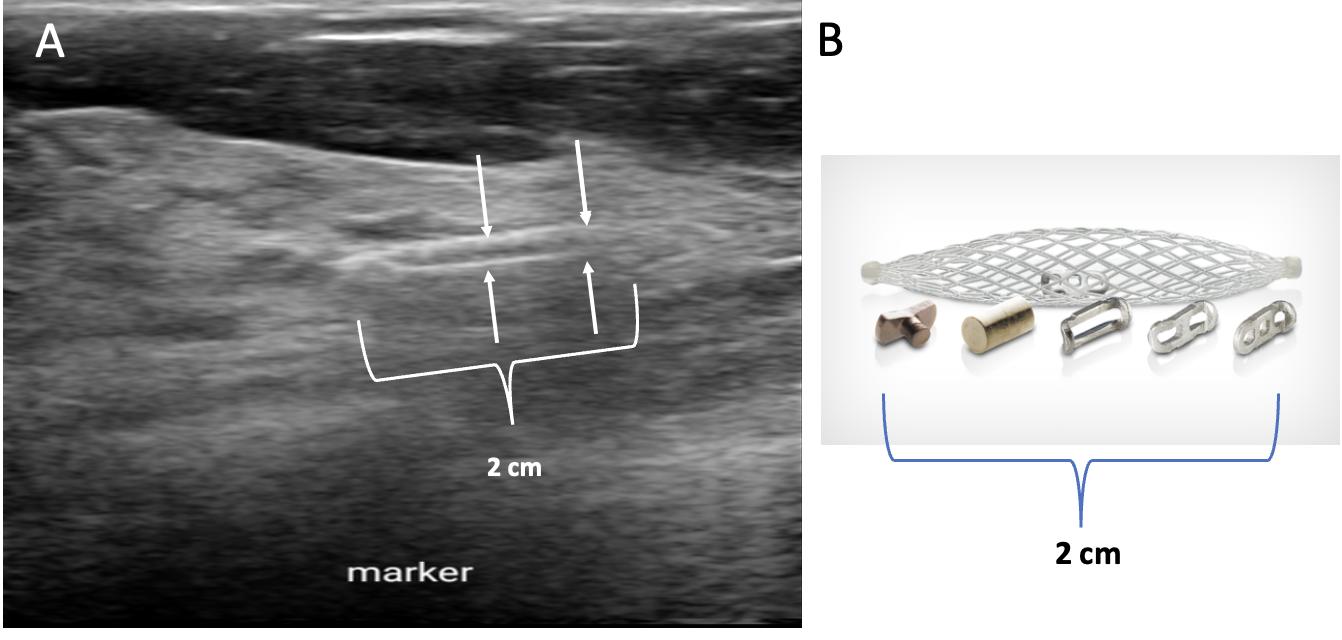

Ultrasound of the breast. Office-based cryoablation is optimized for treatment of ultrasound-visible breast cancers. Consequently, breast ultrasound should be performed of all suspicious imaging abnormalities to assess eligibility for ultrasound-guided cryoablation.

Ultrasound permits assessment of the cancer’s proximity to the overlying skin and underlying chest wall and also enables detection of changes in adjacent tissue architecture (e.g., edema, tissue distortion, extension of tumor into adjacent ducts) and could indicate the presence of more extensive disease that would need to be incorporated into the treatment plan (Image 2).

Proximity (< 5 mm) of a cancer to the skin is generally regarded as a contraindication to cryoablation, but a safe skin distance can sometimes be created using hydrodissection

Image 2. Image A shows dark, dominant, irregular mass encircled by hash marks with intraductal tumor extensions (dark bands bracketed by paired arrows) extending from left and right sides of dominant mass. Image B shows dark, irregular dominant mass (arrow) surrounded by peri-tumoral edema outlined by hash marks